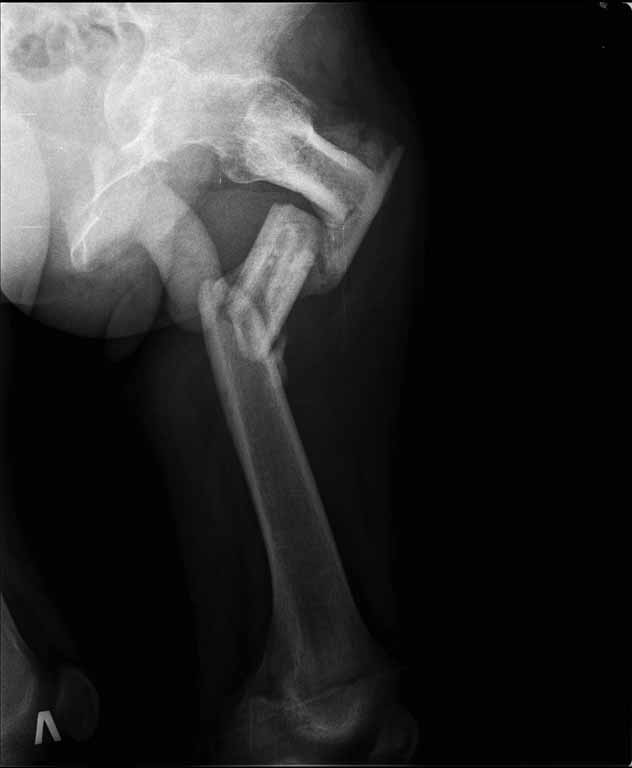

Пациенту 22 года. Травма в июле 2010г, лечился в районной больнице. К нам попал в апреле 2011г.Тяжелая сочетанная травма (29.07.2010): тупая травма живота с повреждением внутренних органов. Закрытая травма грудной клетки с переломом ребер. Пневмоторакс справа. Тяжёлая позвоночно-спинномозговая травма. Закрытый осложнённый переломо-вывих С5 позвонка. Верхний парапарез, нижняя параплегия, нарушение функции тазовых органов по типу недержания. Цекостома. Пролежень левой ягодичной области. Неправильно консолидированные переломы верхних третей обеих бедер. Застарелый вывих левого бедра.Осложнение: Поддиафрагамльный абсесс слева, забрюшинного пространства. Свищ желудка и ободочной кишки. Синегнойный сепсис. Двухстороняя пневмония. Но это уже анамнез.Пациент был неоднократно оперирован на органах брюшной полости и осложнениями с ними связанными.

В ягодичной области слева глубокий пролежень размером 2х2см, дном является вывихнутая головка бедра. Неврологически в нижних конечностях динамика положительная, появились движения в правой стопе, чувствительность в стопах.По переломам бедер: подвижности в местах переломов нет, снимки высылаю.

Уважаемые коллеги, помогите определиться с оптимальной тактикой в лечении перелома бедер. Степень оснащенности у нас достаточная (аппараты, штифты, пластины, ЭОП).

Планирую начать с правого бедра, ЧКО таза (передняя рама) с фиксацией бедра. О/клазия места перелома правого бедра и устранение грубых смещений в аппарате. окончательно можно оставить и в аппарате. Далее аппаратное устранение вывиха левого бедра.